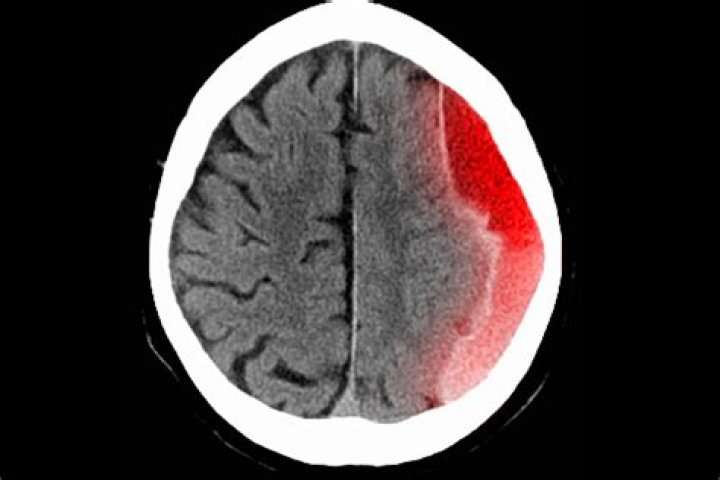

How is subdural empyema diagnosed?

Symptoms of subdural empyema include fever, vomiting, impaired consciousness, and rapid development of neurologic signs suggesting widespread involvement of one cerebral hemisphere. Diagnosis is by contrast-enhanced MRI or, if MRI is not available, contrast-enhanced CT.